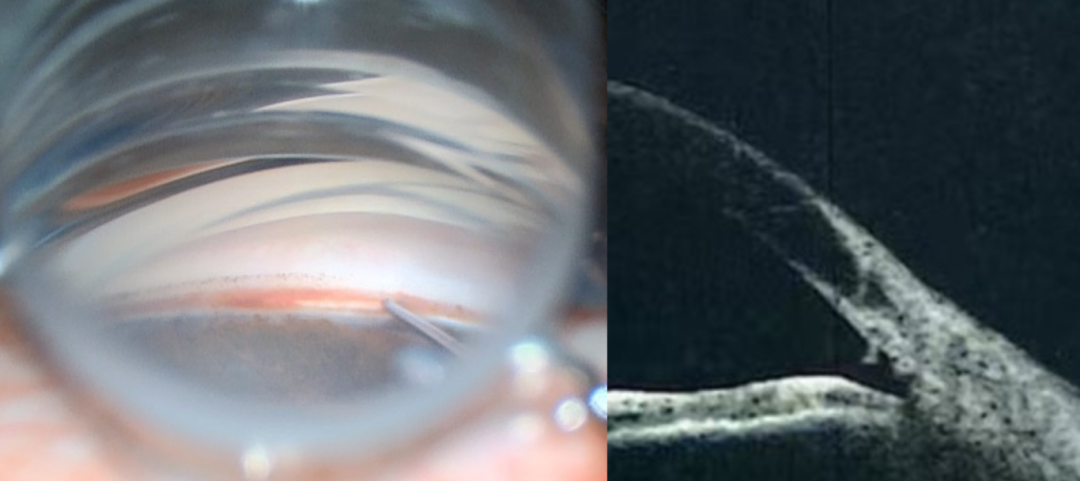

房角镜下的小梁切开术正是MIGS的代表性术式之一。医生在房角镜的清晰引导下,通过仅几毫米的透明微小切口,经眼内路精准划开阻碍房水排出的小梁网及Schlemm管内壁。这个过程,就如同为眼睛被堵塞的“下水道”进行了一次精准的疏通,恢复房水的自然排出通道,从根源上为眼睛“减负”,稳定降低眼压。

59岁的史先生,因眼部外伤导致眼压持续升高,哪怕每天需要滴用三种降眼压药水,眼压仍波动在23-31mmHg(正常范围为10-21mmHg),若还不能及时控制住眼压,恐怕会进一步影响视网膜功能。因此,史先生在医生的建议下接受了房角镜下小梁切开术,术后第一天眼压便降至11 mmHg;一周后,视力明显改善,视野缺损得到控制;术后一个月,已完全停用降眼压药物。史先生感慨:“要是早点知道这个技术,就不用每天惦记着点药水,也不用担心视力一天天变差了!”

68岁的刘阿姨,患有原发性闭角型青光眼合并白内障,病情已发展至中晚期,视力下降已严重影响日常生活,单纯白内障手术也无法解决眼压问题,传统手术风险又较高。在医生的建议下,刘阿姨接受了“小梁切开术+白内障超声乳化联合手术”。术后眼压从术前28mmHg降至14mmHg,白内障也被成功清除。一次手术,解决了两个大麻烦。